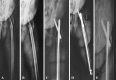

Methods: We conducted a pilot prospective randomized controlled trial comparing standard versus long (≥ 34 cm) intramedullary hip nails for reverse obliquity fractures of the proximal femur from January 2009 to December 2009. There were 15 patients with standard nails and 18 with long nails. Mean age was 79 years (range, 67-95 years). We determined 1-year mortality rates, reoperation rates, Parker-Palmer mobility and Harris hip scores, and radiographic findings (fracture union, blade cut-out, tip-apex distance, implant failure). Minimum followup was 12 months (mean, 14 months; range, 12-20 months).

Results: We found no difference in reoperation rates between groups. Two patients (both from the long-nail group) underwent revision surgery because of implant failure in one and deep infection in the other. There was no difference between the standard- and long-nail groups in mortality rate (17% versus 18%), Parker-Palmer mobility score (five versus six), Harris hip score (74 versus 79), union rate (100% in both groups), blade cut-out (zero versus one), and tip-apex distance (22 versus 24 mm).

Conclusions: Our preliminary data suggest reverse obliquity fractures of the trochanteric region of the femur can be treated with either standard or long intramedullary nails.